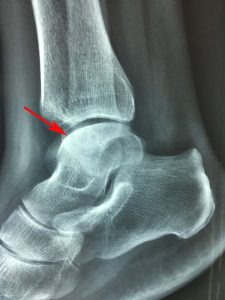

Ο ακτινολογικός έλεγχος (22.7.2019) δια απλών ακτινογραφιών της (Δ) ποδοκνημικής άρθρωσης-άκρου ποδός, ανέδειξε την ύπαρξη οστικής βλάβης στην υπαρθρική περιοχή του αστραγάλου.

Εικόνα 1, α,β,γ,δ

Ακτινογραφίες προσθιοπίσθιες (α & β) και πλάγιες (γ & δ) της (Δ) ποδοκνημικής άρθρωσης. Παρατηρείται υπαρθρική οστική βλάβη στην άνω-έσω γωνία του αστραγάλου. Δεν παρατηρείται καταστροφή των αντιστοίχων αρθρικών επιφανειών αστραγάλου-κνήμης.